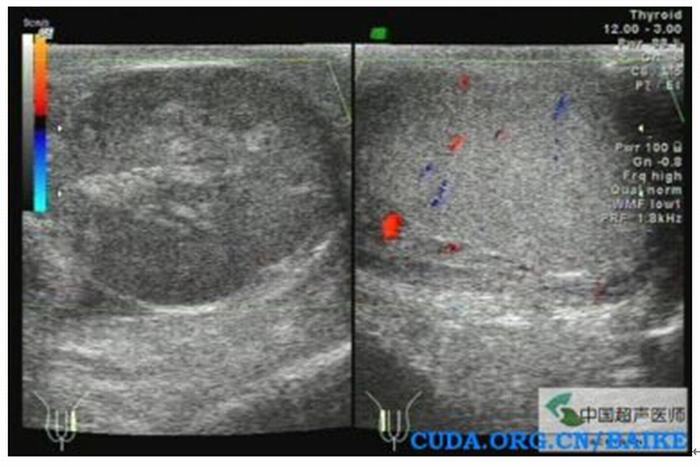

1.多普勒超聲檢查 睪丸血流減少。該方法是目前最快捷和有效的方法。